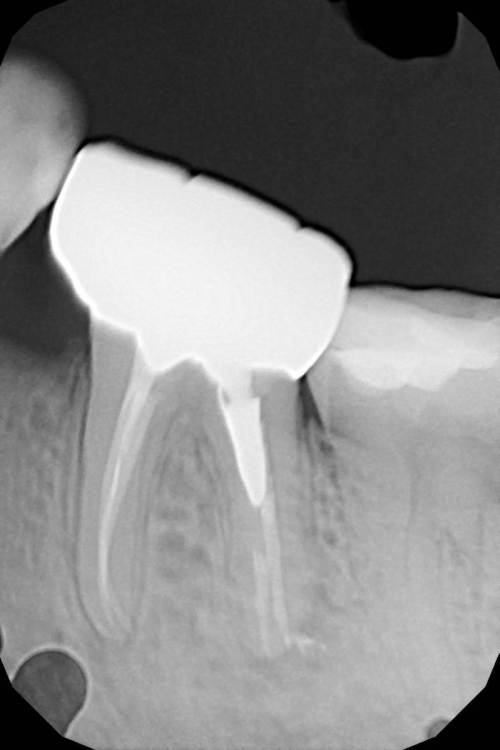

Ico Опубликовано 5 апреля, 2022 Автор Поделиться Опубликовано 5 апреля, 2022 Обострение хронического периодонтита зуб 36. После первичного эндо пропущен ДБ канал,зуб был восстановлен циркониевой вкв + циркон коронка.На пропИл до устья ушло 5 боров.Мед мех стандартный 40к+F1,паковка гибрид с Эйчем.2 визита по 2 и 1.5 часа. 3 1 Ссылка на комментарий